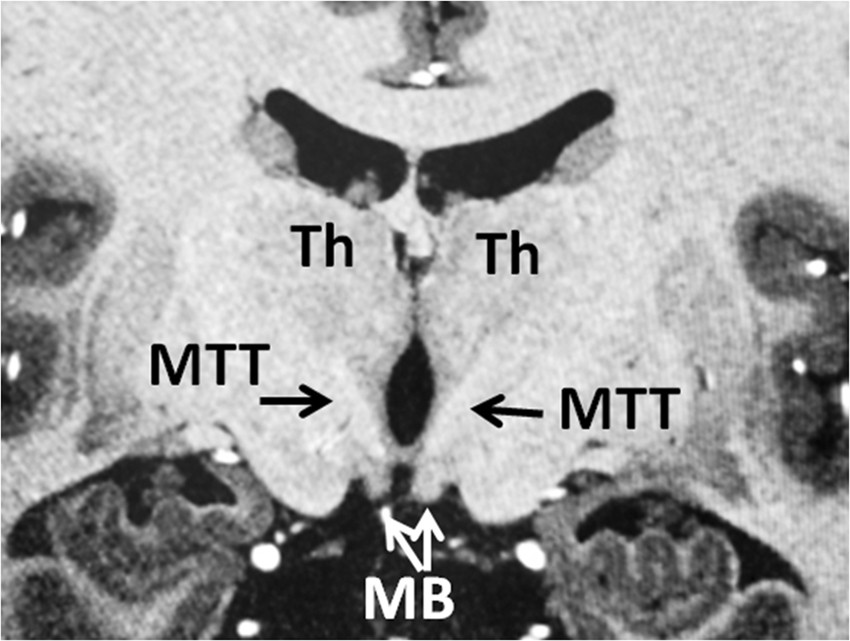

Figure 6

Coronal T1 weighted MRI showing the trajectory of bilateral MTTs on the coronal level just posterior to the mammillary bodies (MB). The bilateral MTTs are visible by T1 hypointense tracts coursing cranially toward the thalamus (Th) after exiting from the mammillary bodies. Please attention that the MTT already projected posteriorly before reaching this coronal level where it ascends into the thalamus. Lateral bendings of the MTTs are visible on this plane as they ascend within the thalami.